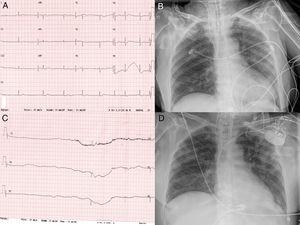

A 75 year-old woman with no previous remarkable clinical history was admitted to hospital with diagnosed COVID-19 diffuse bilateral pneumonia. She was treated with hydroxychloroquine, lopinavir-ritonavir, azithromycin, and methylprednisolone. On day 10 of the hospital stay, she was intubated due to severe hypoxemia. She showed a significant increase of interleukin-6 (105 pg/ml) with normal N-terminal pro-B-type peptide and high sensitive Troponin 1. Interferon beta1-b and tocilizumab were prescribed. On day 33 of the hospital stay, the patient suddenly presented sinus bradycardia and multiple sinus arrest (pauses >10 seconds), Figure 1. An echocardiogram was performed without pathological findings, and a dual chamber pacemaker was implanted without complications. The clinical course was good, and she was discharged from the intensive care unit on day 55 after admission.